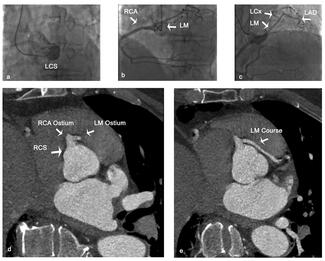

Eleftherios Kontopodis, MD; Maria Kachrimani, MD; Panagiotis Tzortzakis, MD; Kostantinos Vardakis, MD

A 55-year-old man was referred to our department for further evaluation of an episode of syncope with significant elevation of troponin (2.800ng/L) after strenuous exercise. The authors performed a coronary angiography, which showed a single...